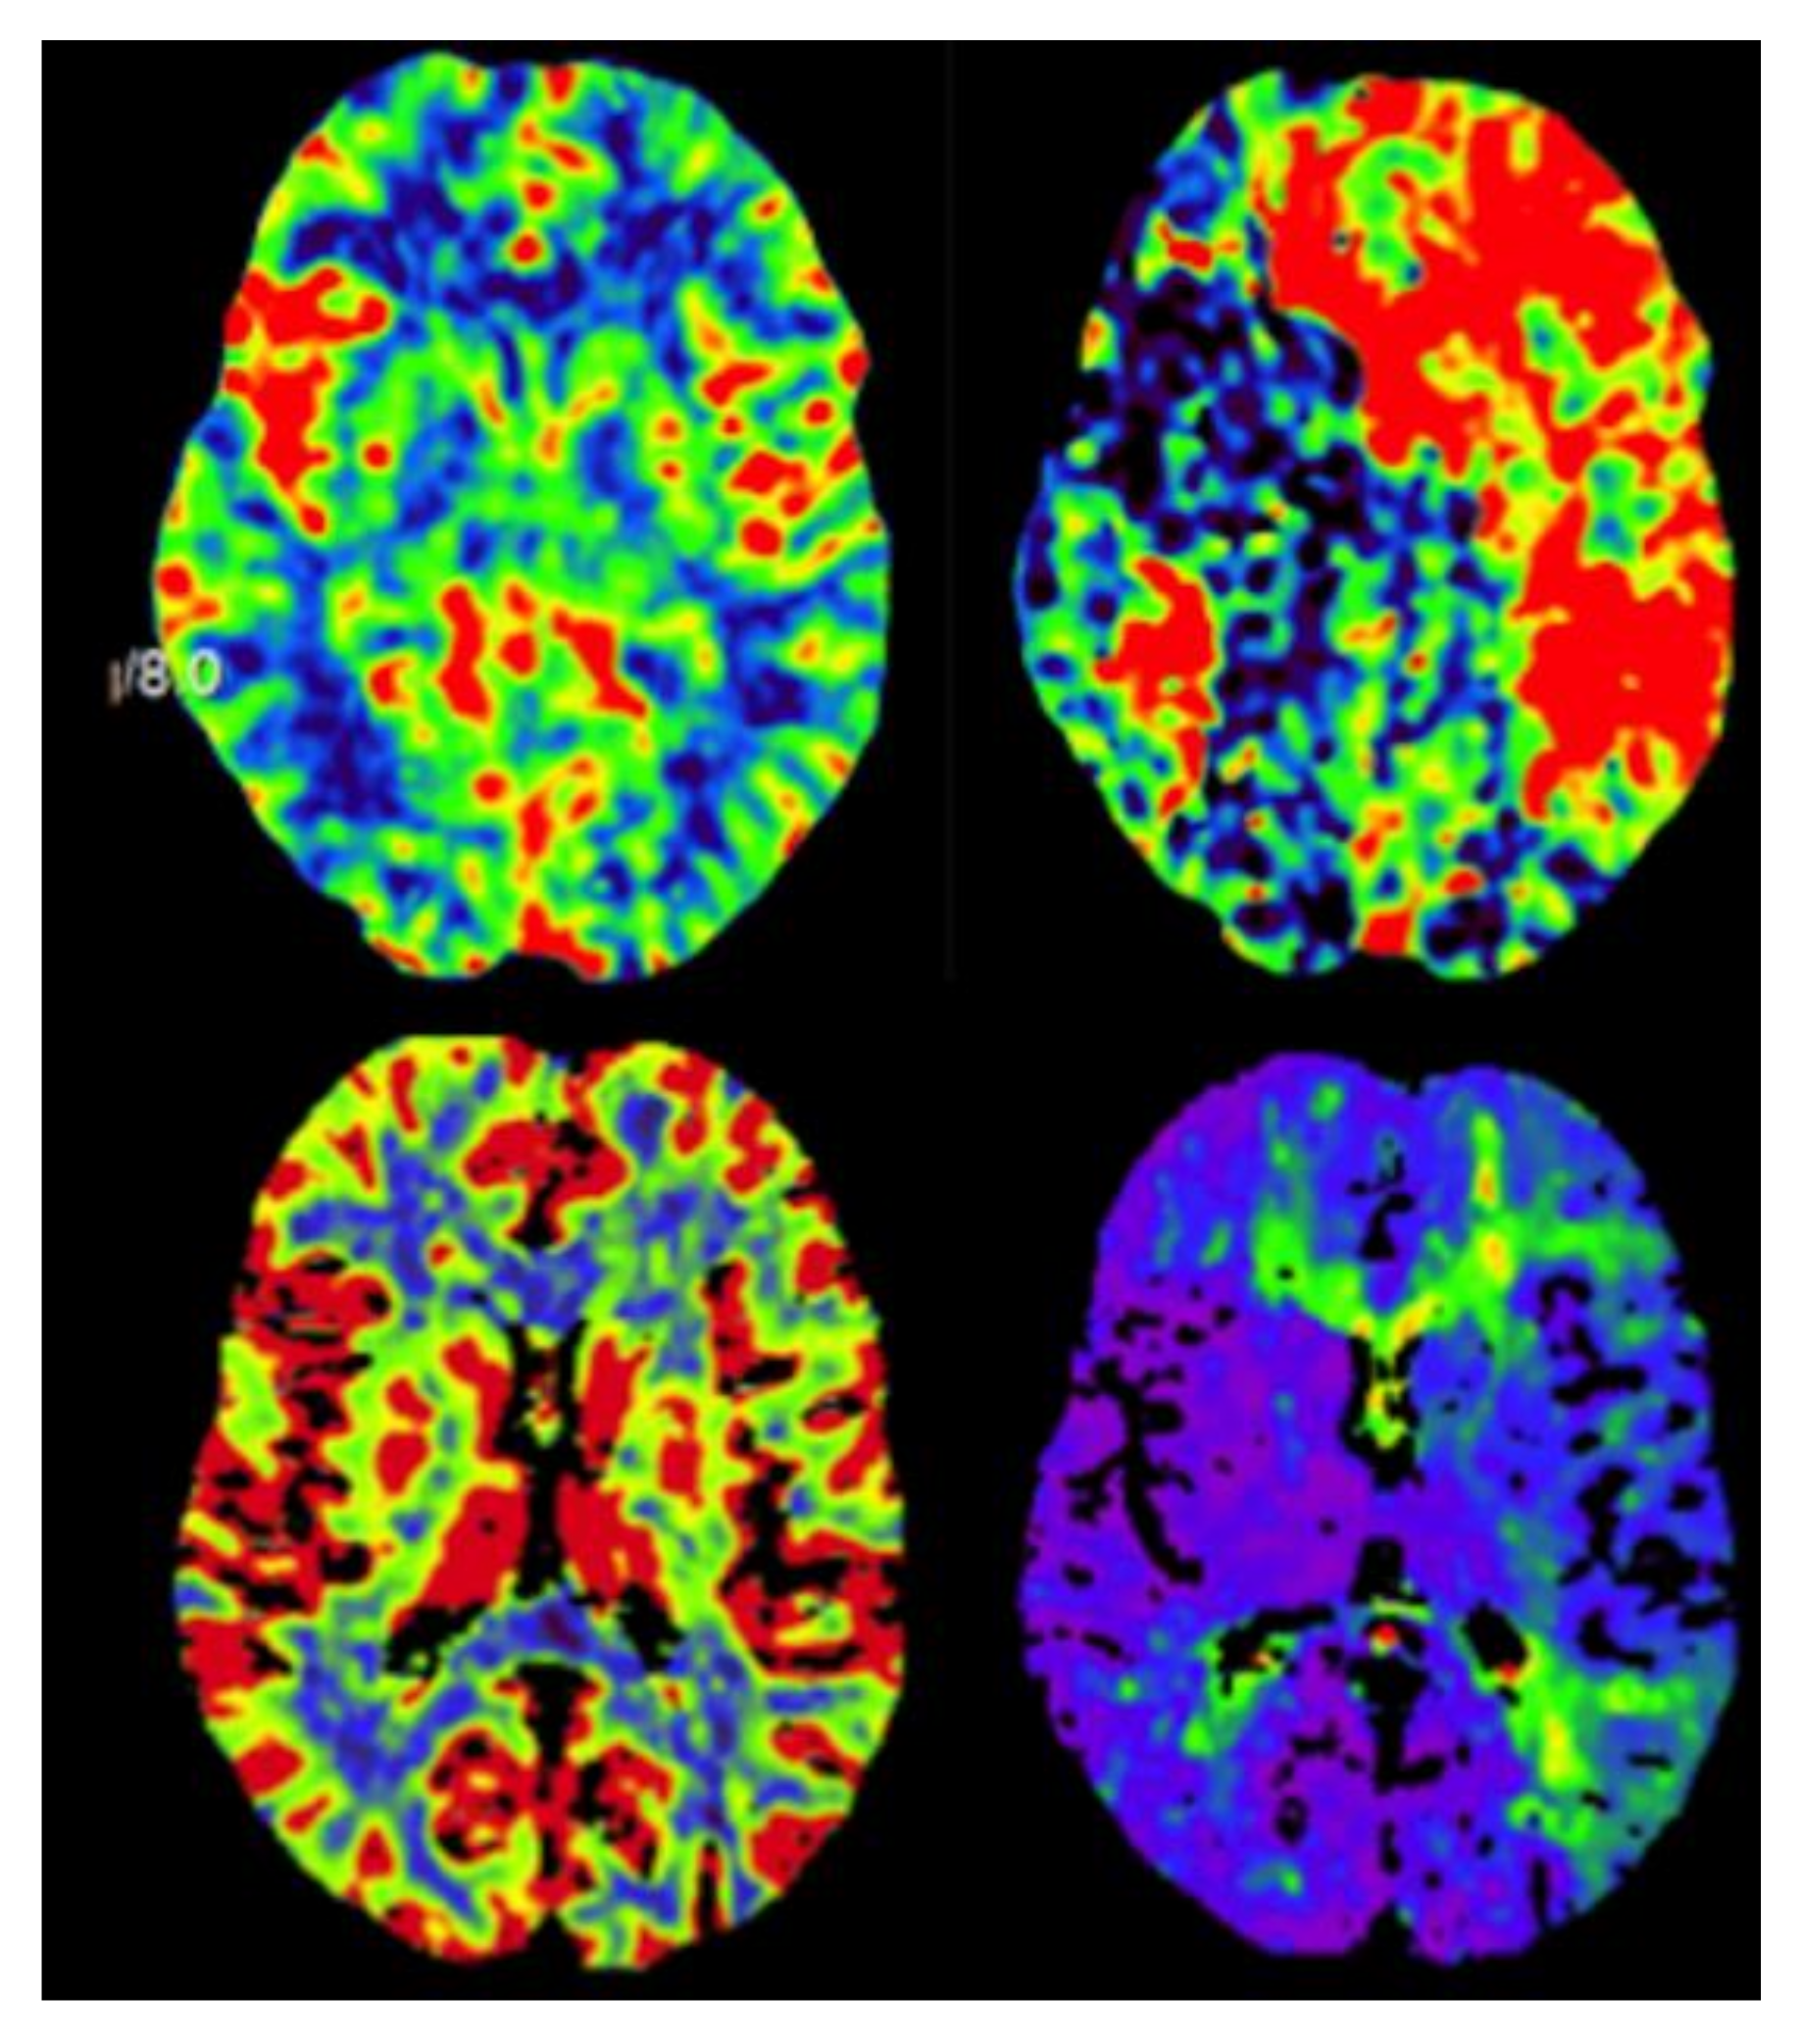

2. Case Description